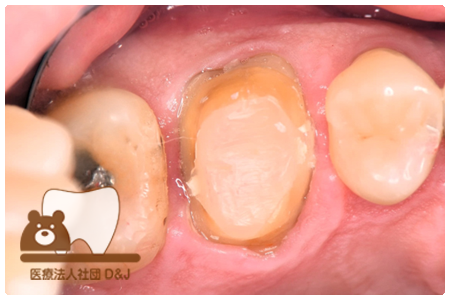

症例8フルジルコニアクラウン

治療前

治療中

治療後

29歳 女性

- 治療内容

- 銀歯からフルジルコニアクラウンへの修復

- 治療期間

- 根の治療含め3か月

- 費用

- 自費

フルジルコニアクラウン:77,000円(税込)

- その他の治療の費用は含まれておりません。

- リスク・副作用

- 強い衝撃が加わると欠けたり割れたりする可能性があります。また、噛み合わせの状態によっては脱離や周囲の歯への影響が出ることもあります。